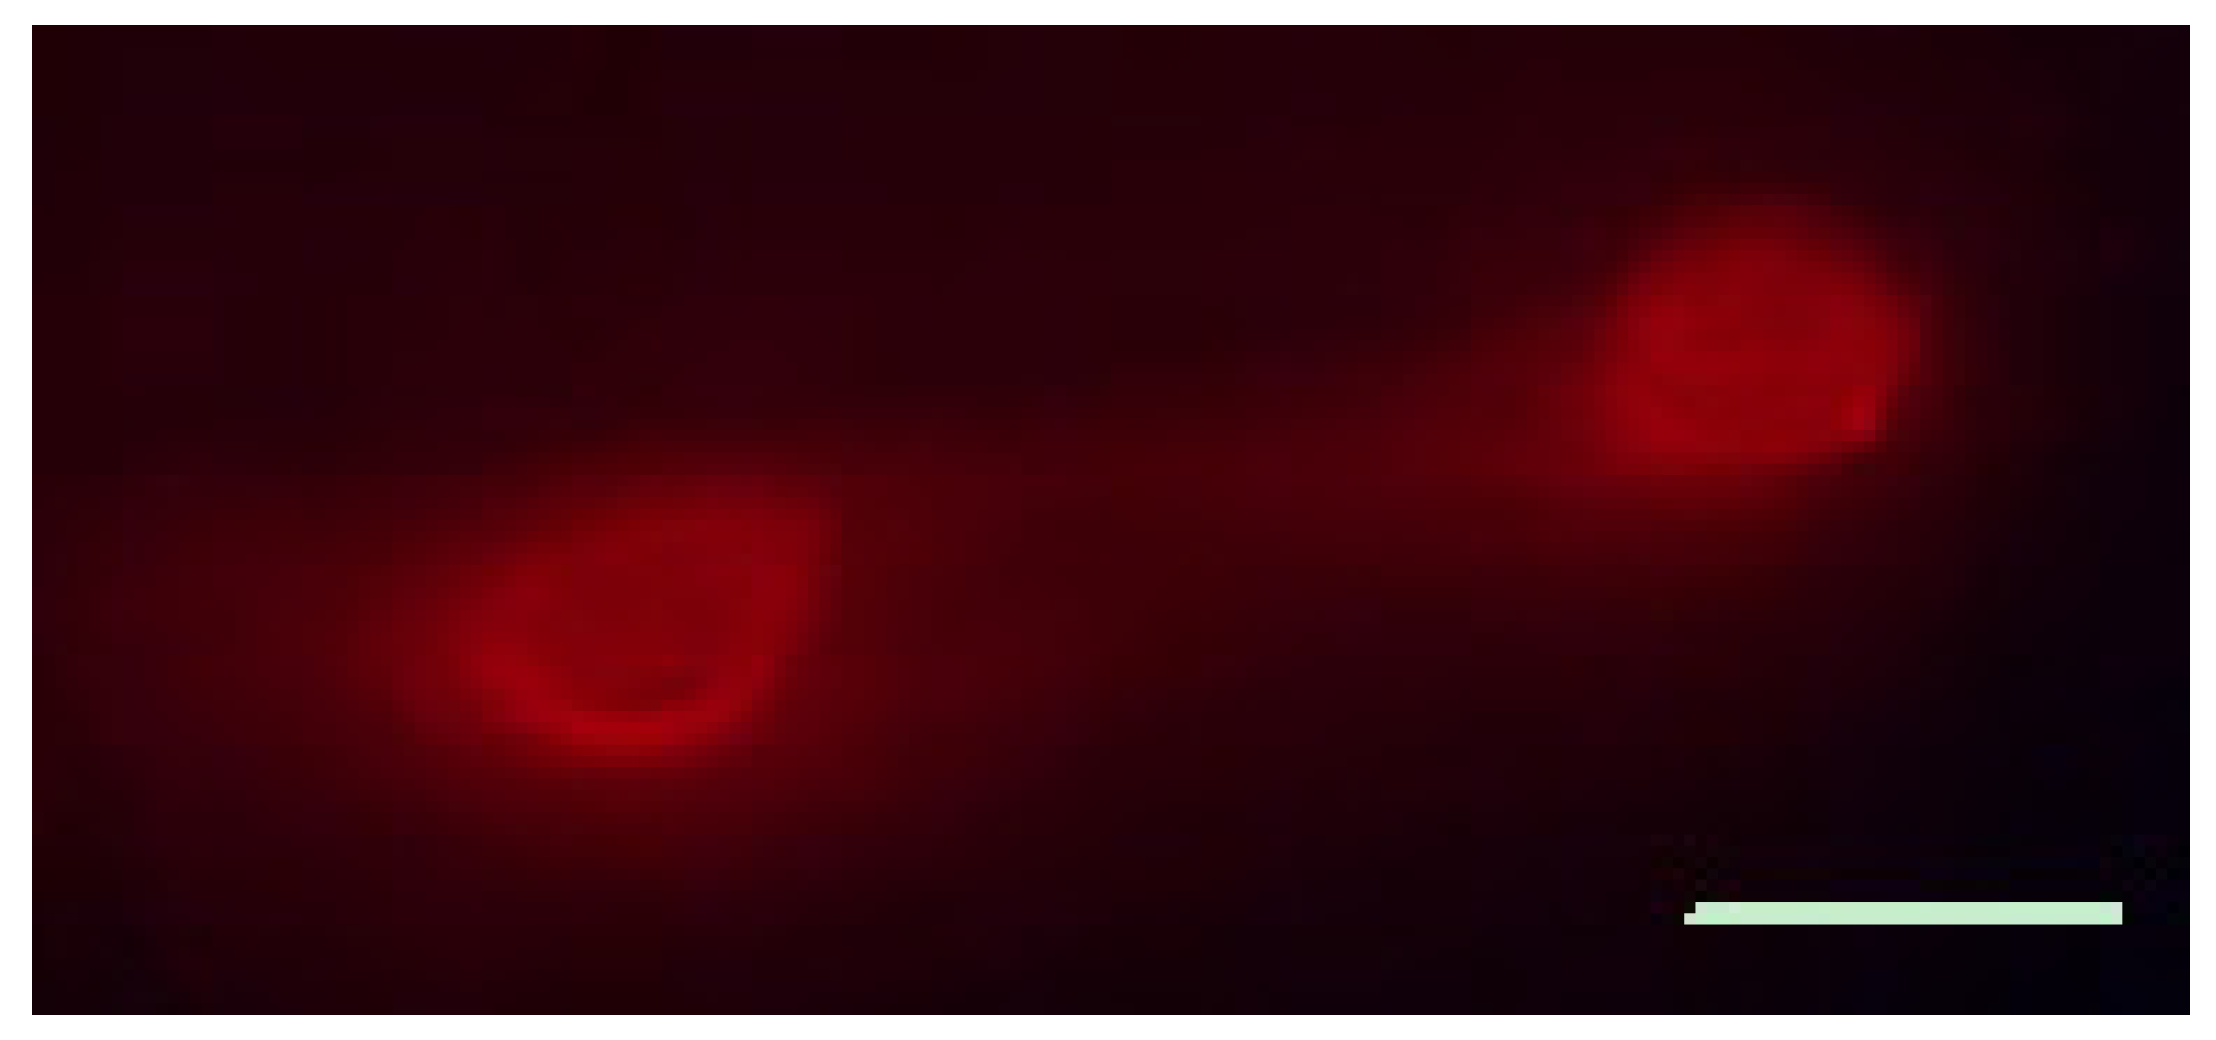

3.6. Calcium Imaging of SGC Responses to ATP